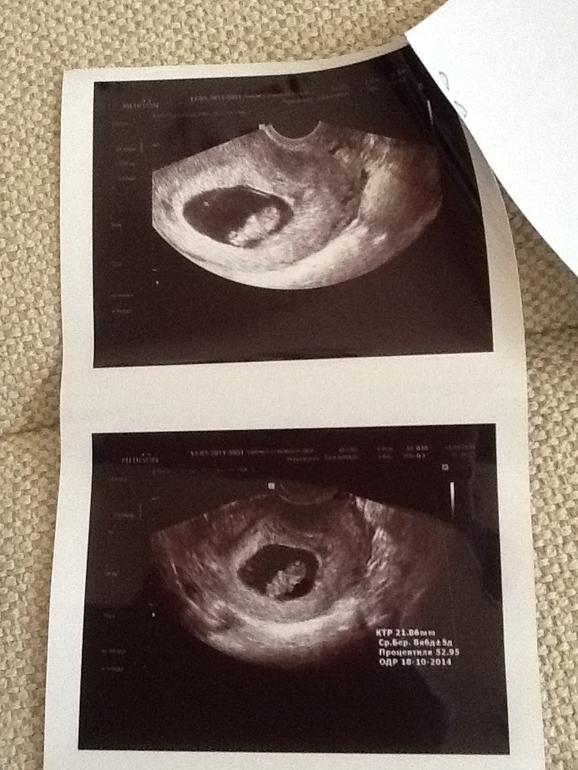

Девочки, привет. Вот, наконец, села написать о нас) Сегодня нам ровно 9 недель от М, аппарат узи выставил 8 недель 6 дней) КТР 22 мм - соответствует сроку 9 недель. ПДР 18.10.14, а у нашего папы ДР 19.10))) будет папочке драгоценный подарочек. Вообще, это уже второе узи, первое было в 6 недель, чтобы установить факт маточной Б и сердцебиение. Следующее узи планировала уже в 12 недель, но не тут-то было...В своем дневнике я жалилась, что нет никаких признаков Б. Ага, щас(( они тут же появились, после 6 недель. Это просто ужас какой-то, а на токс(( первые две Б можно сказать, летала, как птица. а сейчас - постоянная тошнота, есть ничего не могу, сбросила 2 кг, только пью. Слава Богу, хоть неприятных последствий тошноты нет! и еще скачет давление( даже скорую один раз вызывала - 140 на 110, при моем-то 90 на 60. И стал тянуть низ живота. вот и поскакала сегодня на УЗИ, чтобы посмотреть, все ли хорошо с моей крошечкой после такого моего трехнедельного состояния нестояния. Да, все хорошо, ттт!!! только тонус небольшой, отсюда боли. Увеличили дозу магния. ЧСС 171)) врач сказала, что это отличная частота. Где-то гуляла на просторах ББ теория про пол ребенка по ЧСС. Какие будут предположения? 9 недель ЧСС 171. (первая дочка ЧСС 143, но это в 12 недель, вторая - 160)А вообще, наверное, не зависит, все это индивидуально. Ну и фотки моей крошки))